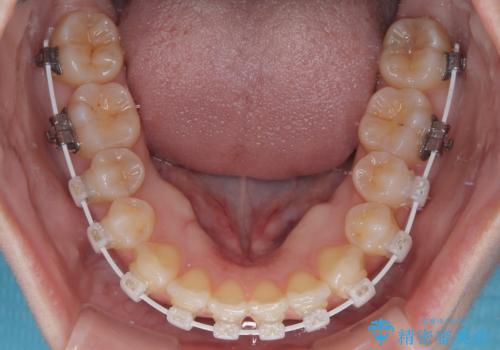

- 審美装置

- 1年4ヶ月

- 10-30回

1年と少しで矯正治療を終えることができ患者様は大変満足されました。